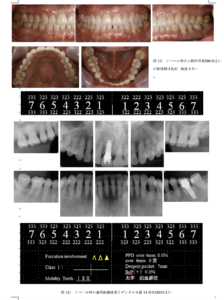

臨床歯周病学会投稿論文4 症例の概要患者:56歳, 女性 初診:2008年 11月 主訴:上顎右側中切歯の動揺 全身的既往歴:特記事項なし, 非喫煙者. 歯科的既往歴:上顎右側中切歯は20歳の時に打撲し抜髄・補綴治療を受けた. 今まで修復治療は行ってきたが, 歯周病の治療は受けたことがない. ここ十数年未治療であった. 口腔内所見:口腔衛生状態は不良. すべての歯に, 歯肉の発赤・腫脹が認められた. 7 6 , 7 6 , 6 7, には6mm以上のポケットが認められ, 7 6 6 7にⅠ度の, 1 にⅡ度の動揺があった. 4mm以上のポケットは45.3%, Bop(+)は44.0%, PCRは100%であった. また, 6 近心にⅠ度の根分岐部病変を認めた. 上下顎臼歯部に修復物があるが, 辺縁は不適合で2次カリエスが認められた. 上顎には口蓋隆起, 下顎にも下顎隆起が見られ, すべての歯の周囲が外骨症であった. エックス線所見:全顎的に中等度の水平性骨吸収が認められ, 765 567と765 345 に垂直性骨吸収があり, 1 には歯根吸収, 6 には歯根破折と思われる骨欠損が根尖にまで及んでいた. 家族歴:両親とも当クリニックでメインテナンス中であり, 重度の歯周炎はない.

4) 口腔機能回復治療 1 6 ともに, インプラント埋入3ヵ月後にアバットメント( 図9 f, 図10 e )とプロビジョナルレストレーションを装着し, さらに3ヵ月後に最終補綴を装着した. インプラント補綴より3ヵ月後の再評価期間をおいて, SPTに移行した(2011.2.). また, ブラキシズムへの対応としてナイトガードを装着した. 5) SPT 現在は3ヵ月に一度の来院でSPTを継続している.が, 歯肉の発赤, 腫脹も認められず, 深い歯周ポケットも認められない. デンタルエックス線写真では, 一部骨様組織が認められる部位もあるが, 歯槽硬線の明瞭化も認められ骨の平坦化及び安定が図られた. 夜間においては, スタビライゼーション型スプリントの装着を行い, ブラキシズムに対応している. 6 7 に関しては, SPT移行1年後, 咬合調整を行った. 8年後の再評価(2019.2.)において, PPD 3mm以内, BoP(+)は認められず, 歯周組織の状態は安定していた( 図11,12 ). PCRは7 %であった.